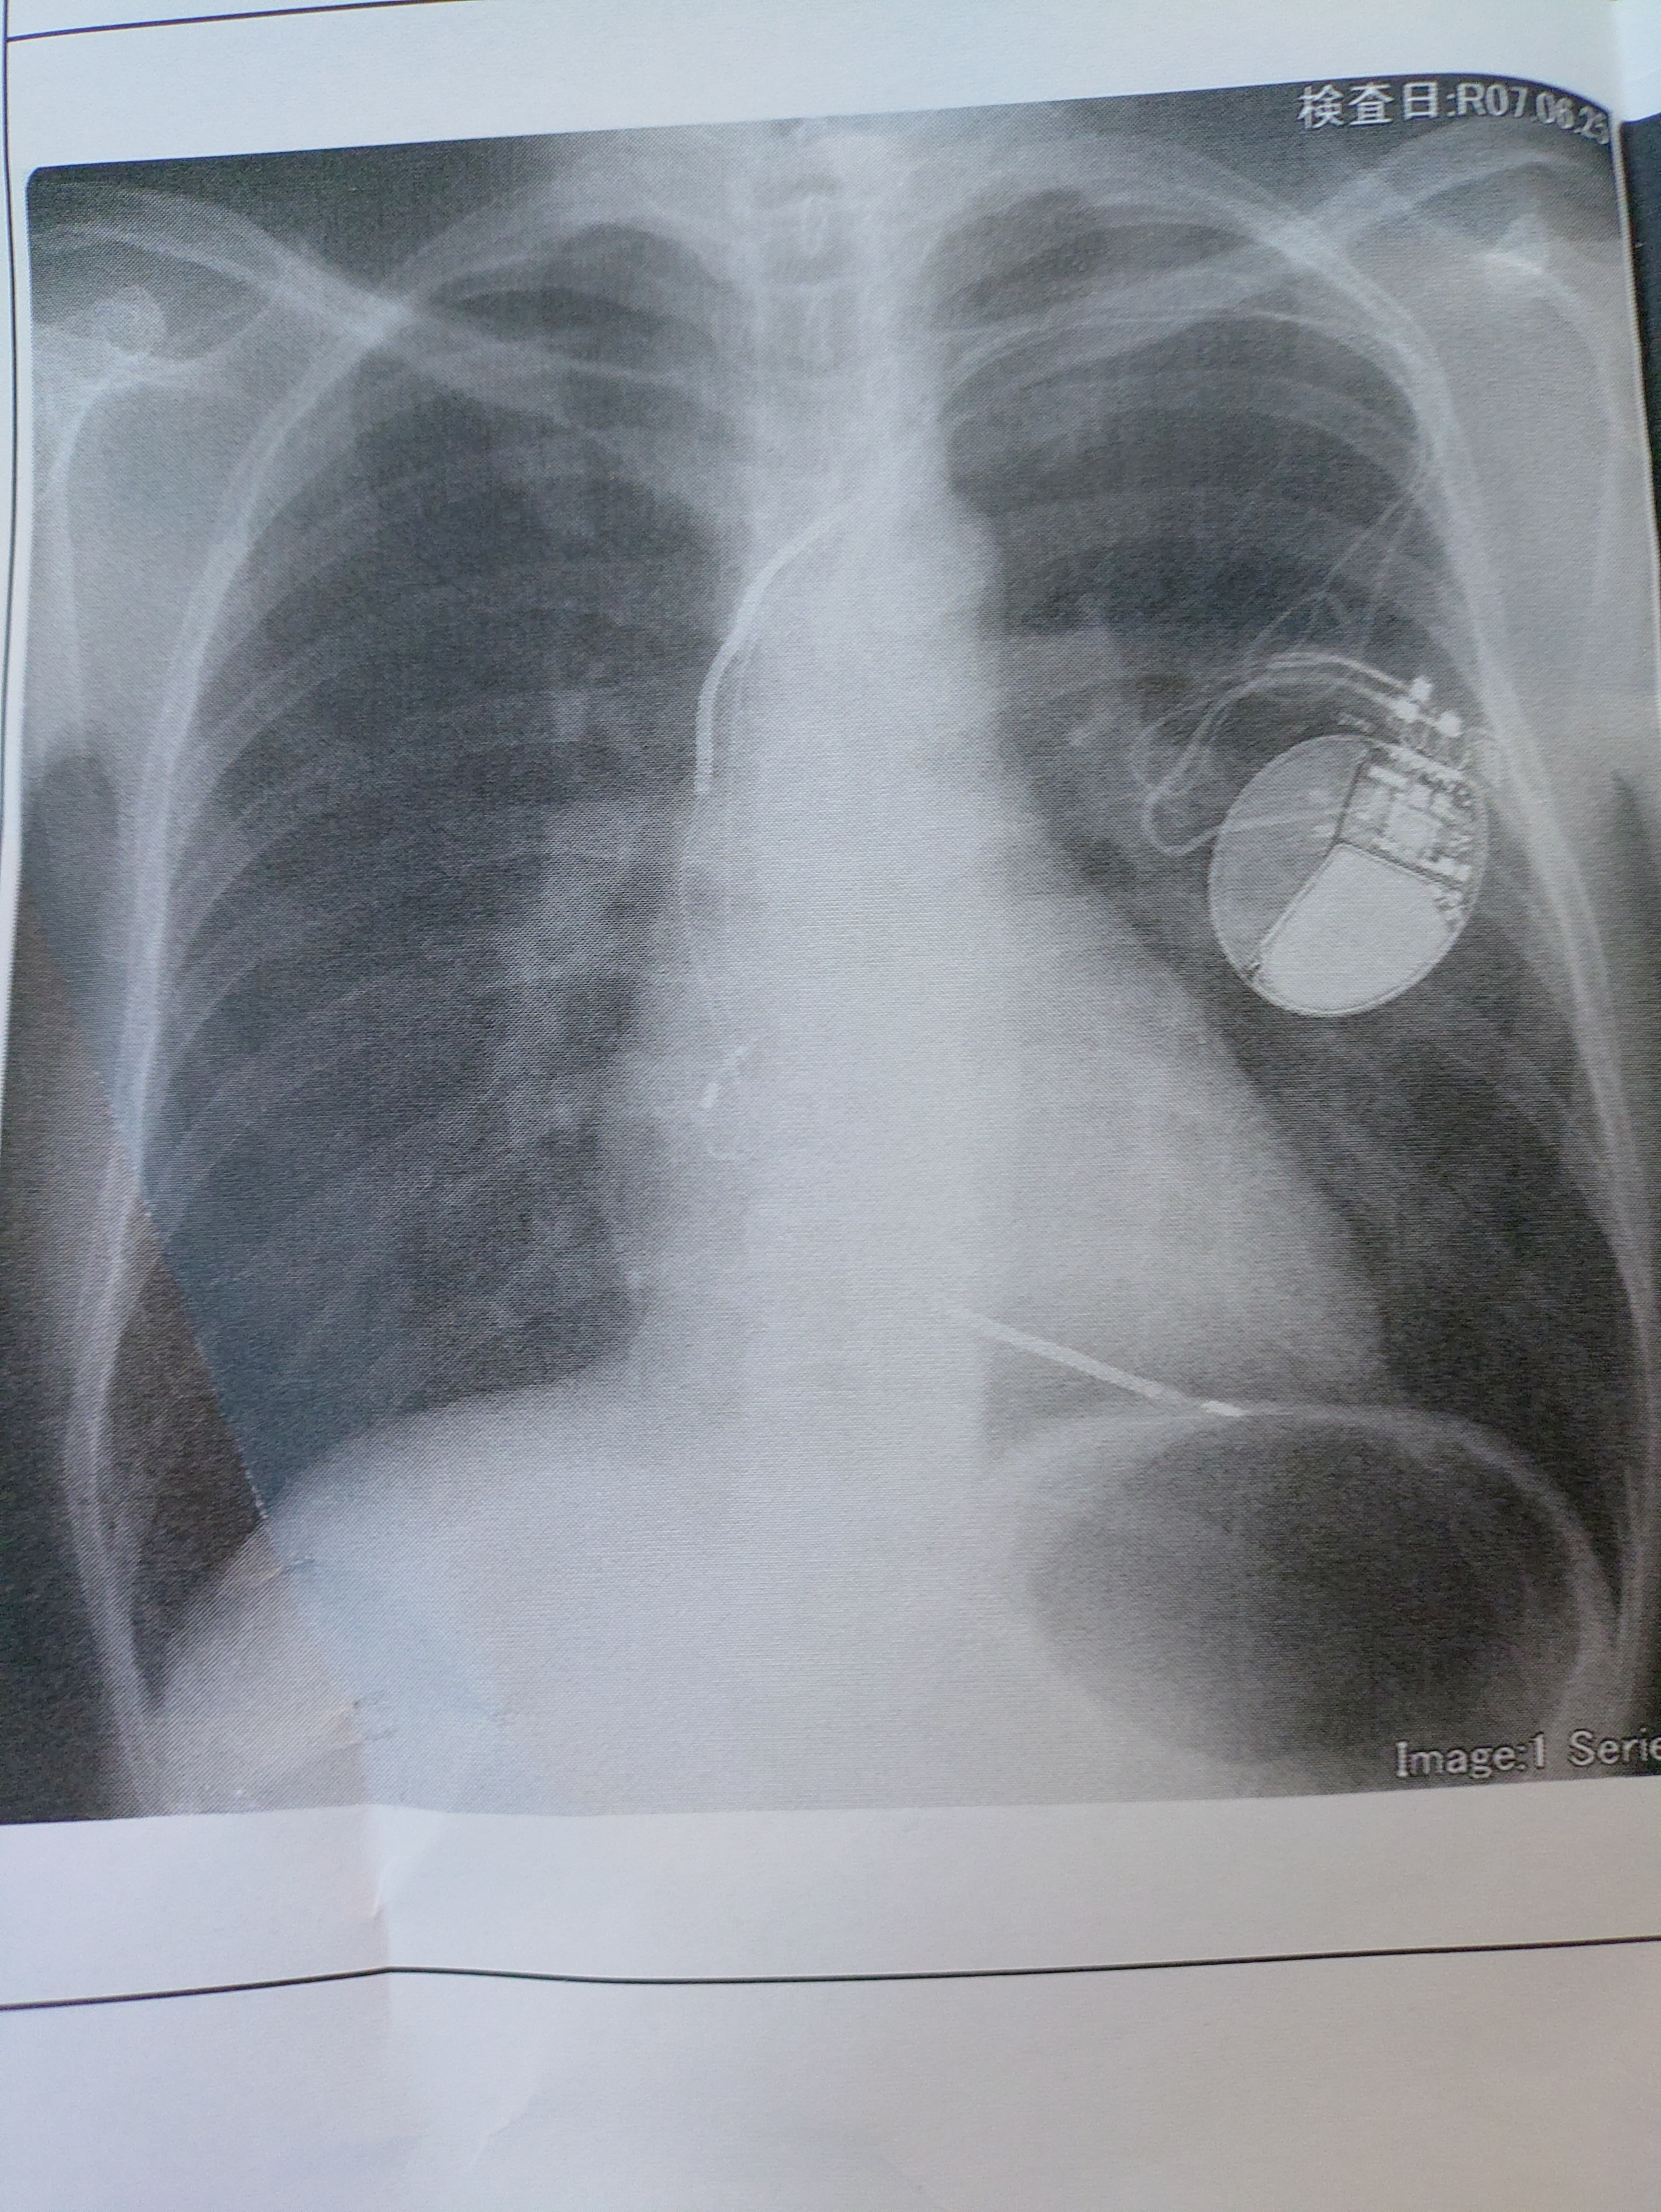

トップ > TORQUEフォト > ICD ボストンサイエンティフィック 退会したユーザー 2025/06/25 19:48 ICD ボストンサイエンティフィック 植え込み型除細動器、ペースメーカー AED付きのペースメーカー 前はバイオトロニック いいね 共有する 共有する X facebook LINE リンクをコピー コメントする 2 件の返信 (新着順) ミュートしたユーザーの投稿です。 投稿を表示 にしもん@50s pro 2025/06/25 21:03 電池交換必須💥😀💦🍺 やっぱりその度に入院なんですか❓️ いいね 返信する ミュートしたユーザーの投稿です。 投稿を表示 退会したユーザー 2025/06/25 21:36 にしもん@50s pro 入れ替え手術だね、その後3週間は入院、その間は病院のショップに行くにも許可が必要で、10分以内に戻って来なさいだったよ いいね 返信する ミュートしたユーザーの投稿です。 投稿を表示 退会したユーザー 2025/06/25 21:46 こんな傷で心臓に近いから感染したら、1ヶ月以上放って置いたら心臓感染で死亡するらしいから納得いくけどね 高齢者は2ヶ月は掛かるらしい いいね 返信する ミュートしたユーザーの投稿です。 投稿を表示 退会したユーザー 2025/06/25 22:16 にしもん@50s pro 拡大図を忘れてた、ここで2回目だけど見てみて いいね 返信する ミュートしたユーザーの投稿です。 投稿を表示 にしもん@50s pro 2025/06/26 10:38 退会したユーザー ウチの父親も2ヶ月位入院するようです😅☕ まぁ真夏回避出来ていいんじゃ無い❓️ ついでに禁煙も出来る😀👍 いいね 返信する ミュートしたユーザーの投稿です。 投稿を表示 退会したユーザー 2025/06/25 19:49 いいね 返信する ミュートしたユーザーの投稿です。 投稿を表示 やまのきのこ 2025/06/25 19:54 退会したユーザー 良いね押しましたが、病気だったんですね?何とコメントしてよいのかわかりませんが、生涯装着されることになるんでしょうかね。 ご自愛ください。 いいね 返信する